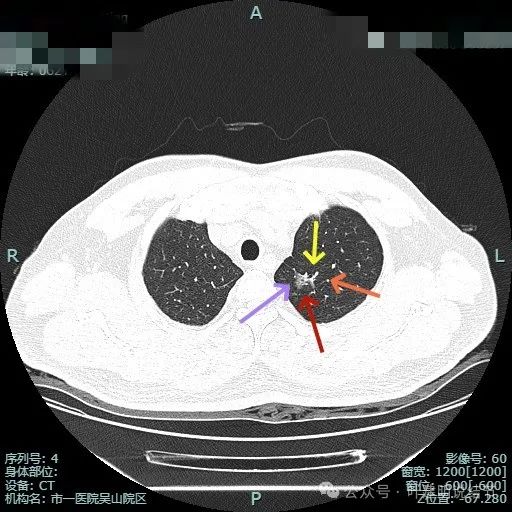

薄层影像:

病灶出现,瘤肺边界清,表面不平有分叶。

灶内密度不纯,整体轮廓清,瘤肺边界清楚。

明显分叶以及血管贴边并有异常增粗。

边缘毛刺,血管进入,灶边有细支气管扩张,整体轮廓与边界清。

血管异常增粗进入,灶内小空泡征,表面不平有浅分叶,灶内密度感觉欠均匀。

血管进入,边缘细毛刺,灶内小空泡,少许实性成分,表面不平毛糙。

似有月牙铲征,显得像混合密度。

边缘区域表面不平。